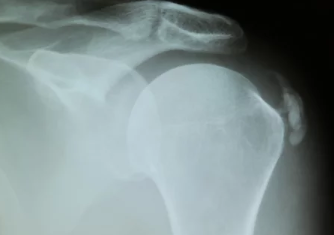

- X-ray(엑스레이):

- 석회질의 위치와 크기를 확인하는 가장 기본적인 검사